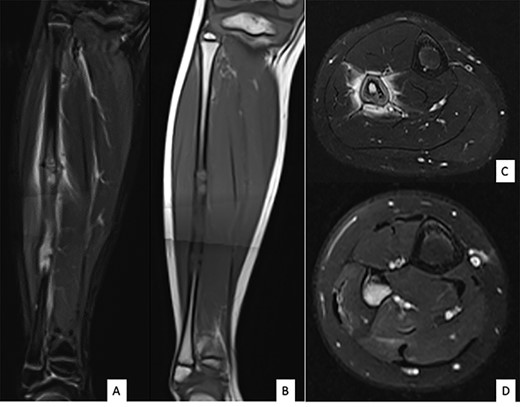

Ultrasound showed a diaphyseal subperiosteal hematoma of the fibula with cortical irregularities. The radiograph showed a pathological fracture, at the upper end of a cortical bone lesion of mixed osteolytic and osteoformative character with bone callus (Fig. 1). MRI showed a multifocal osteolytic cortical process extending along the fibular shaft, without tumor mass in the soft tissues with respect for the signal of the medullary cavity. The perilesional soft tissues were respected, but they appeared in strong hypersignal T2 and enhanced after injection of gadolinium (local inflammatory reaction or post-traumatic changes; Fig. 2).

Anteroposterior (A) and lateral (B) radiographs of right fibula showing pathological fracture on a cortical bone lesion of mixed osteolytic and osteoformative character with bone callus.